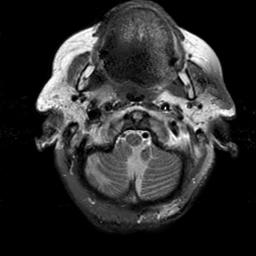

To demonstrate the effectiveness and efficiency of the proposed image fusion method , we conduct a set of comparative experiments on three image datasets. The first is composed by 8 pairs of multi-modal medical images and the second one contains 15 pairs of multi-focus gray or color natural images. These two datasets are often used in many related papers and some examples are shown in Figure 3(a) and Figure 3(b). The third one is a new multi-focus cervical cell image dataset collected by ourselves, which consists of 15 groups of color images and each group contains a series of multi-focus cervix cell images with size of or , etc. Some source examples are shown in Figure 3(c). Our source code implemented in C++ along with the new multi-focus cervical cell image dataset is available online.

We first evaluate the performance of the proposed method under varying total number of octaves and number of layers sampled per octave. The fused images of a pair of multi-modal medical images with different and are shown in Figure 4. In this example, on the one hand, when only 1 or 2 octaves are involved in constructing the DoG pyramid, the fused images fail to keep the integrity information of large size objects (e.g. eyeballs), while by increasing the value of , the integrity information of eyeballs is preserved. On the other hand, although not as significant as the increase of octave numbers , the fused image can contain more details by the increase of layer numbers . The corresponding objective quality metrics are shown in Figure 5. As shown in Figure 5(a), most of the metric values are improved as the number of octaves increases with the fixed layer numbers 3 in the global tendency and each of them tends to be stable when the number of octaves is 5. To get a relatively good quality from Figure 5(b), we can notice that some of the metric values can get a good performance when the number of layers is 3, such as the MI, SSIM, QI and VIF, though there are only a little change of all the metric values by increasing the number of layers with the fixed octave numbers 5. Because it will result in more computation burden with the increase of the value and , and for different kinds of source images, there are different performance with the diverse parameter settings. To get a trade-off between them in our experiments, we set for the multi-modal dataset, for the natural datasets and for the multi-focus cell dataset, respectively.

Figure 6 shows the fused images obtained by different methods with the multi-modal source images shown in Figure 3(a). As shown in these figures, the proposed method can produce images which preserve the complementary information of different source images well. Moreover, due to the scale-invariant structure saliency selection, our method can keep the integrity information of large size objects and the visual details simultaneously. Although the fused image generated by other methods can also capture the details to some extent, all of them fail to keep the integrity information of large size objects such as the eyeballs. Furthermore, from Figure 6(k)-6(t), the DTCWT, GFF, IM and NSCT methods may decrease the brightness and contrast while the proposed method can preserve these features and details without producing visible artifacts and brightness distortions.